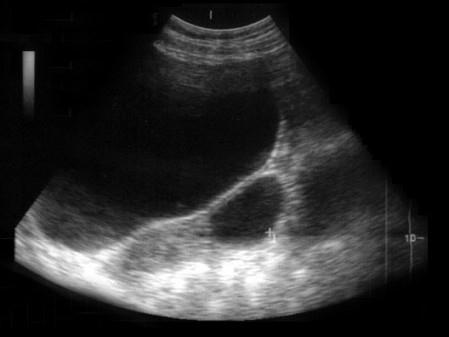

患者女25岁, B超检查如图所示应诊断为 ( )A、左卵巢囊肿B、左卵巢巧克力囊肿C、左侧输卵管积液D、左卵巢卵泡E、左卵巢Ca

问题 患者女25岁, B超检查如图所示应诊断为 ( )

选项 A、左卵巢囊肿 B、左卵巢巧克力囊肿 C、左侧输卵管积液 D、左卵巢卵泡 E、左卵巢Ca

答案 A